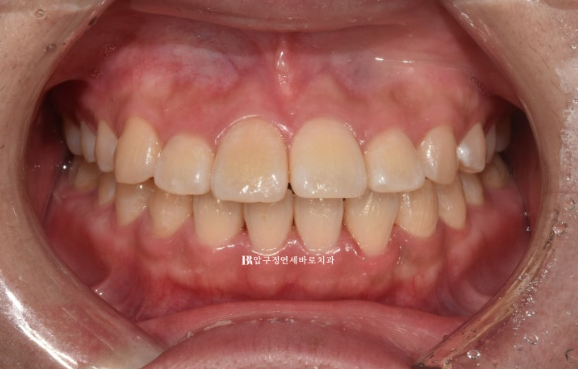

10년 전 어릴때 비발치 교정을 했던 환자분입니다.

치아는 가지런하고, 어금니도 잘 씹히는데 재교정을 원하는 이유는 <앞니 뻗침> 때문이였습니다.

23.04